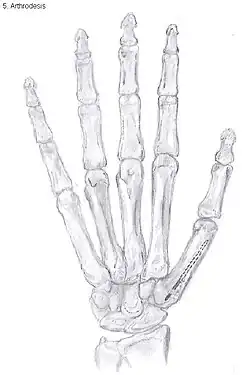

Arthrodesis of the thumb

Arthrodesis

Arthrodesis of the TMC joint is a surgical procedure in which the trapezium bone and the metacarpal bone of the thumb are secured together. They are held together by K-wires or a plate and screws until the bone will heal.

Disadvantages include inability to flatten the hand.[23] Additionally, the stress on the CMC joint is now spread over the adjacent joints, those joints are more likely to develop osteoarthritis.[30]

Nevertheless, this procedure can be used in patients with stage II and III CMC OA as well as in young people with posttraumatic osteoarthritis.[23]